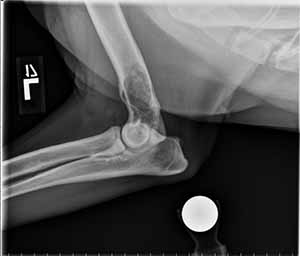

Radiographs of the left elbow show the following:

Lateral view: